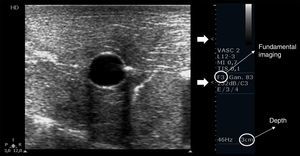

Depth, gain and focal zones are the most important machine parameters that practitioners always need to optimize to carry out the best possible evaluation on the vessels. Preferably, tissue harmonic imaging must be switched off, especially for further needle recognition8 (see below) (Fig. 2).

Proper basic technical parameters to optimize the image for vascular cannulation. The focus zones, which are two in this case (arrows), are positioned in superficial tissues and in line with the vessel, so as to improve resolution in these regions, thus best delineating the vessel and its surrounding structures and further recognizing the needle and its insertion in the vessel. Depth must be adjusted involving the vessel posterior wall and the structures behind it, in order to select or discard a vessel for cannulation (e.g. artery over vein overlapping) and to readily detect an inadvertent puncture of the vessel posterior wall. Proper gain adjustment (general gains and near-far field gains using the time-gain compensation controls) are essential: too high gains can mask the echogenicity of the needle between the tissues, while too low gains may obscure the echogenicity of the needle as well as the vessel. Finally, using fundamental imaging is advocated, since tissue harmonic imaging is associated with poorer needle recognition.